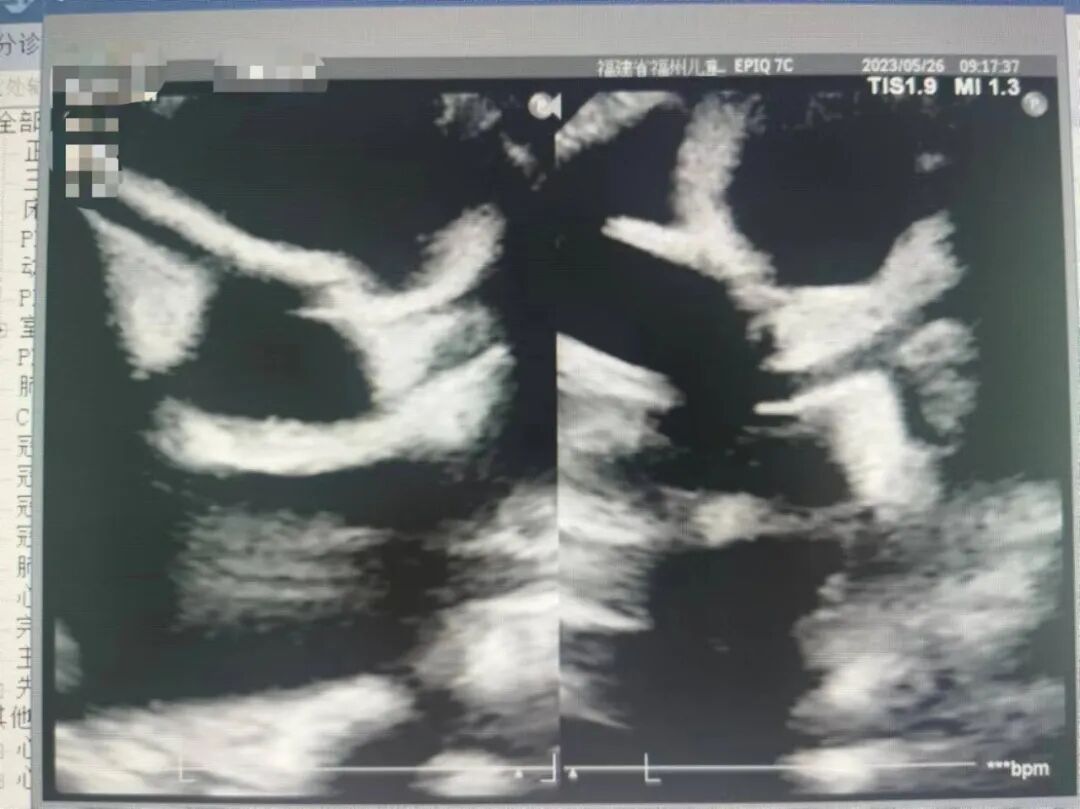

临床的主要症状和体征医生可以通过问诊发现,但是心脏方面的症状起病比较晚,病程比较隐密,表现多见于心包炎、心肌炎、心内膜炎和心律失常,一般发生于病程的2-4周,最重要也是最常见的是冠状动脉的损害。超声心动图对冠状动脉扩张和冠状动脉瘤形成的诊断具有特异性,能清晰测量冠状动脉内径,扩张程度,而且随访观察简便易行,成为诊断冠状动脉损害的首选方法。

超声心动图在川崎病诊断及随访中的有哪些作用?

1、协助川崎病的诊断

2、冠状动脉损害的诊断

3、心脏并发症的诊断